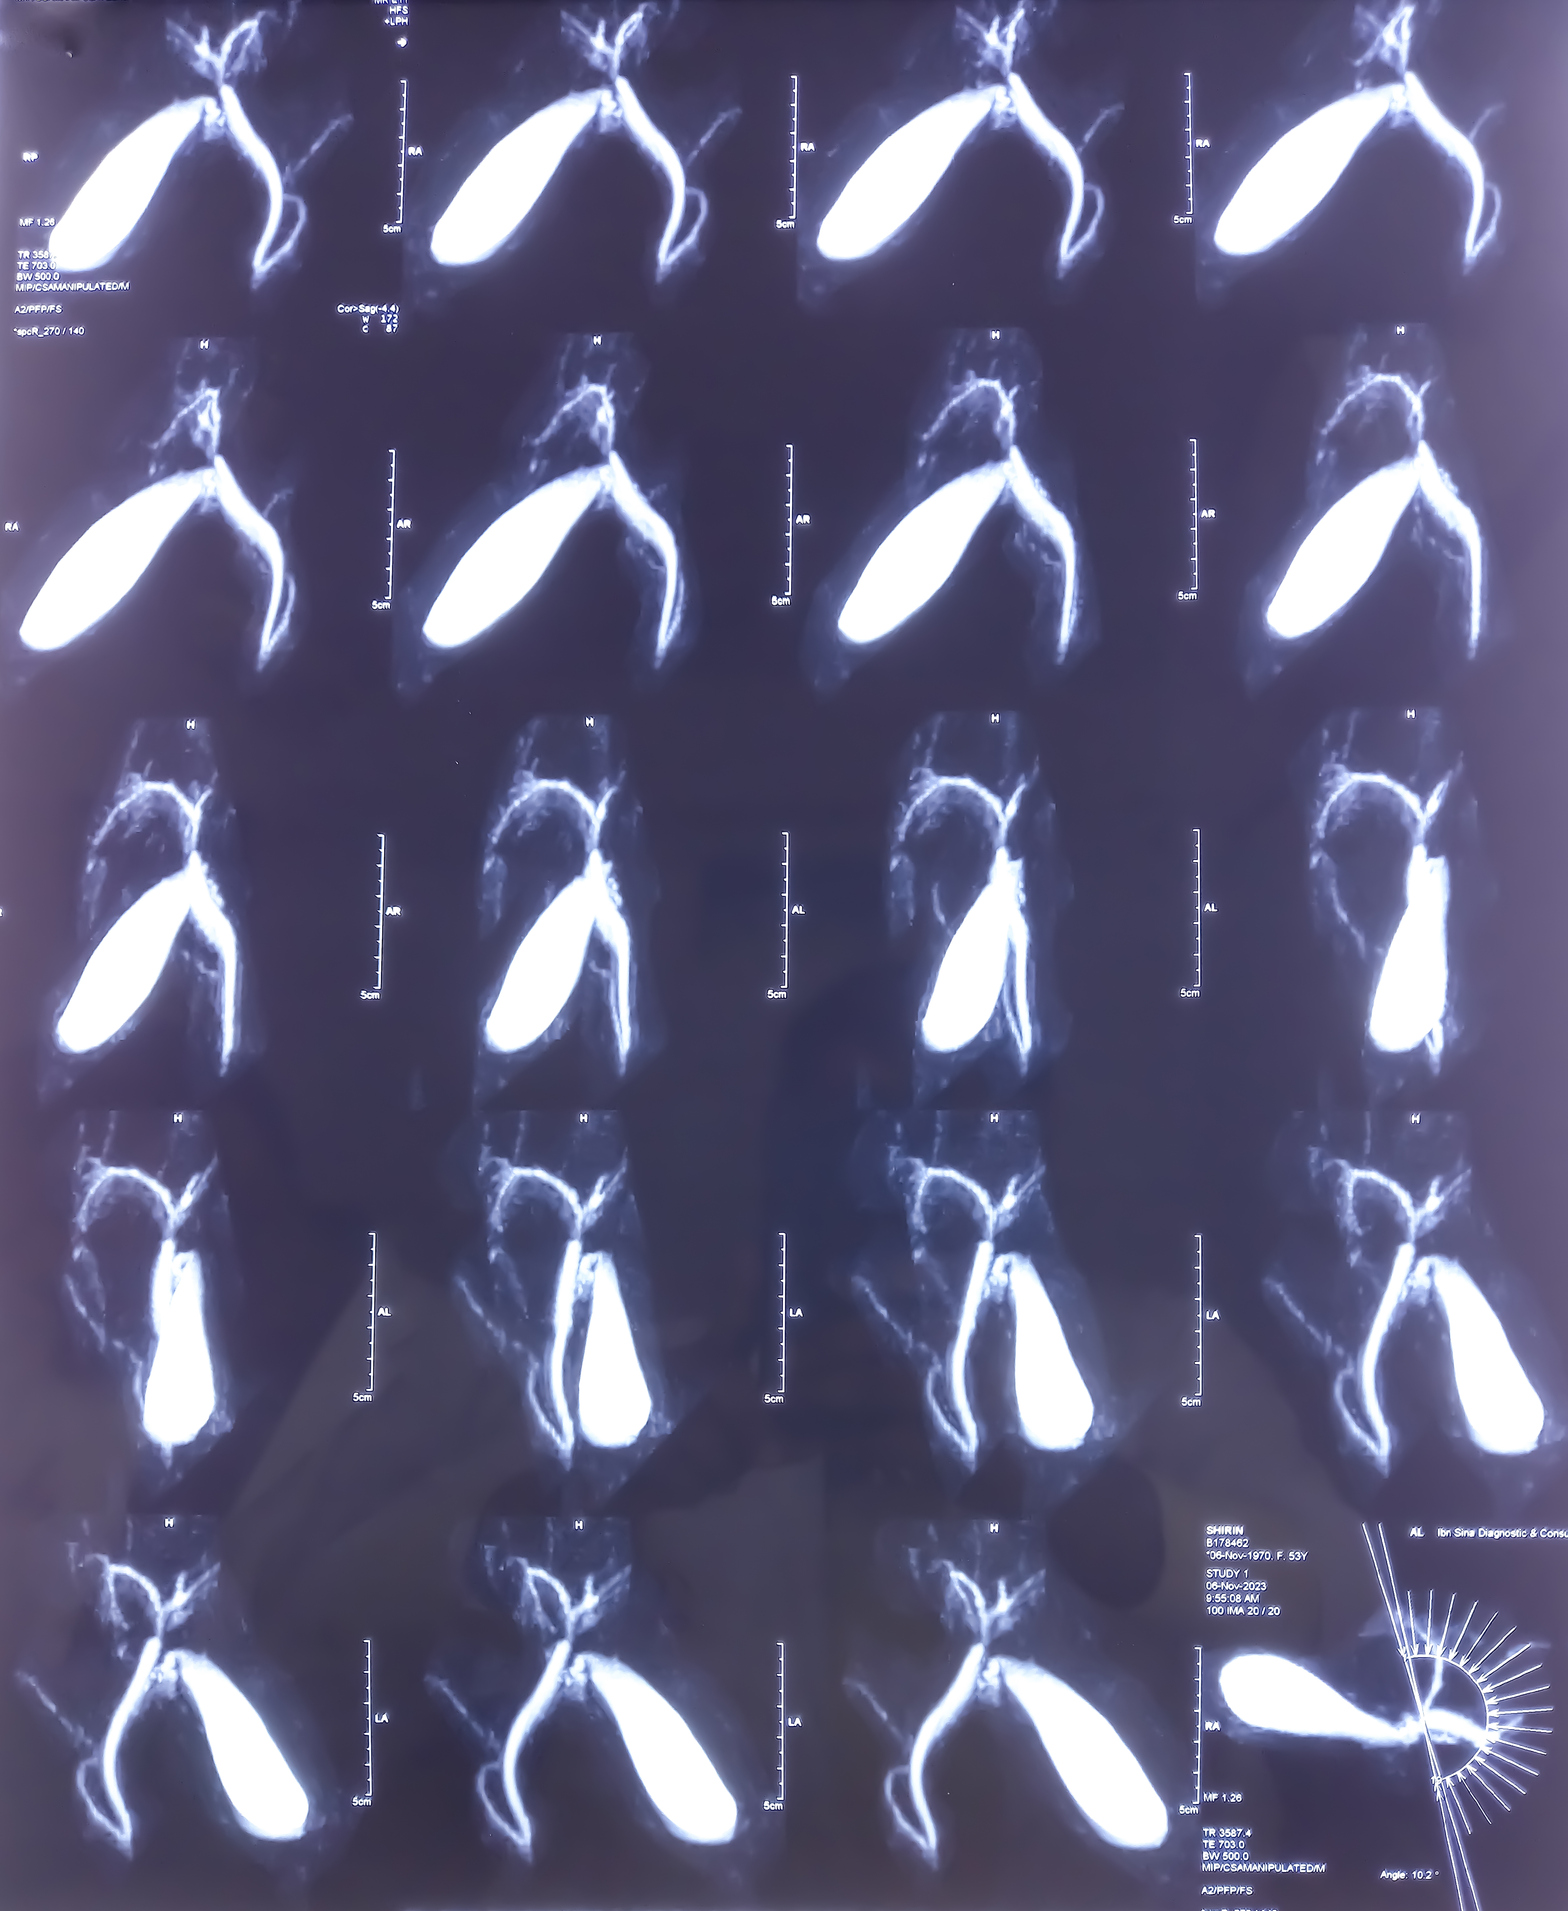

To successfully diagnose Bile Duct Cancer several procedures may be used, including: